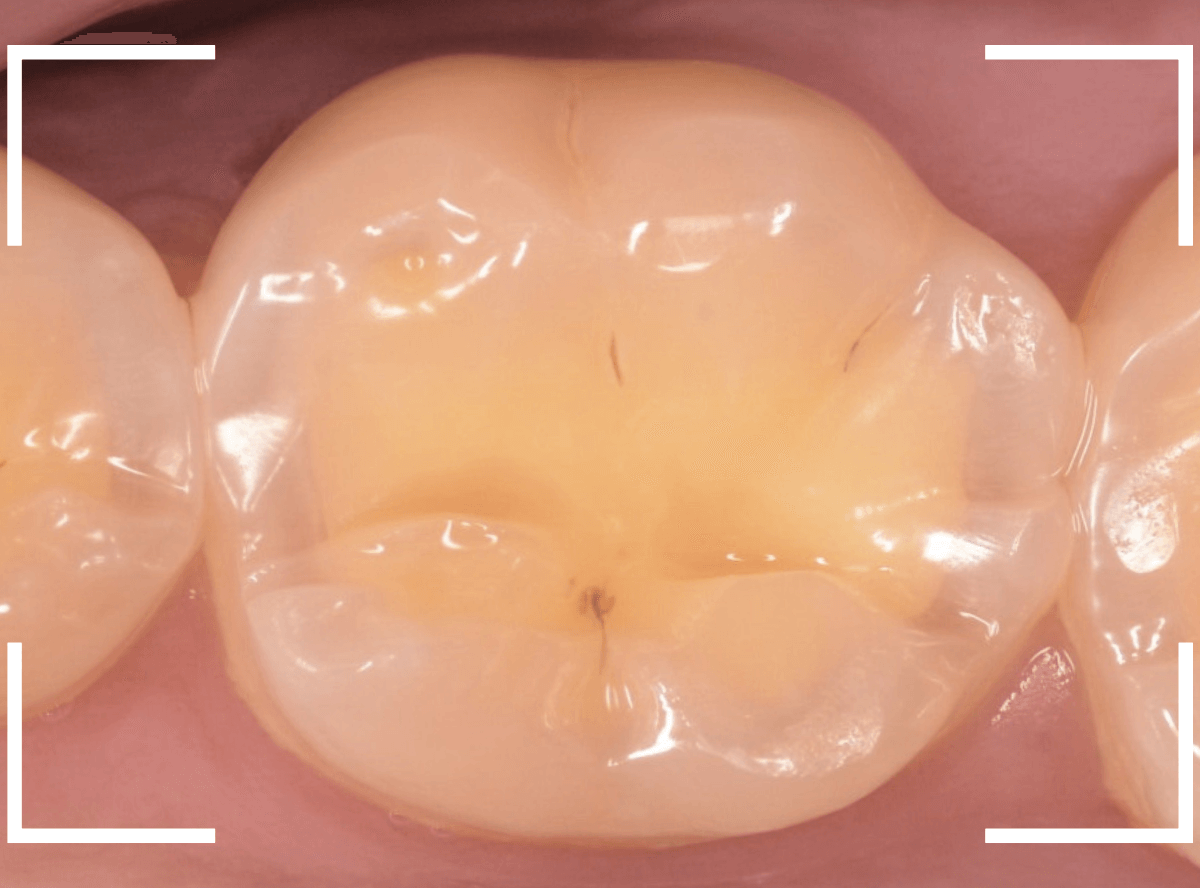

知覚過敏の方は歯の側面がしみるケースが多いですが、今回は側面もしみるが、かみ合わせの面(咬合面)もしみるといいます。

しみる歯を拝見して「ちょっとこれは難しいケースかもしれないな」と思いました。

さて、なにが難しいかといいますと、

赤線の部分、歯の溝にあたる部分がかけてるというよりも、不自然に鋭角にえぐれている状態です。

くいしばりなどかみ合わせの力がここに不自然に集中してる可能性が高く、「何かスポーツなどされてますか?」とやんわりお聞きすると、心当たりがあるのか「職場で重い物を持ってくいしばる事が多いです」との事でした。

レントゲン写真で歯を確認します。

特に中に異常はなさそうですが、油断はできません。

このように大きな力がかかった歯にはレントゲンや見えない傷がついてたりする事もあります。

すると、不定期にしみや不快感が起こる事もあり、原因がわからず途方に暮れてしまう事もあるのです。

今回は幸運にもえぐれている部分にレジンを薄くつめる事で症状はかなり緩和されましたが、かみ合わせで短期でレジンが剥がれてしまう事も大いに考えられます。

できれば、マウスピースを作製し、日中も歯を保護してほしいですが、仕事中は難しいそうです。。。

状況を説明し、定期的に経過観察に来院してもらう事になりました。